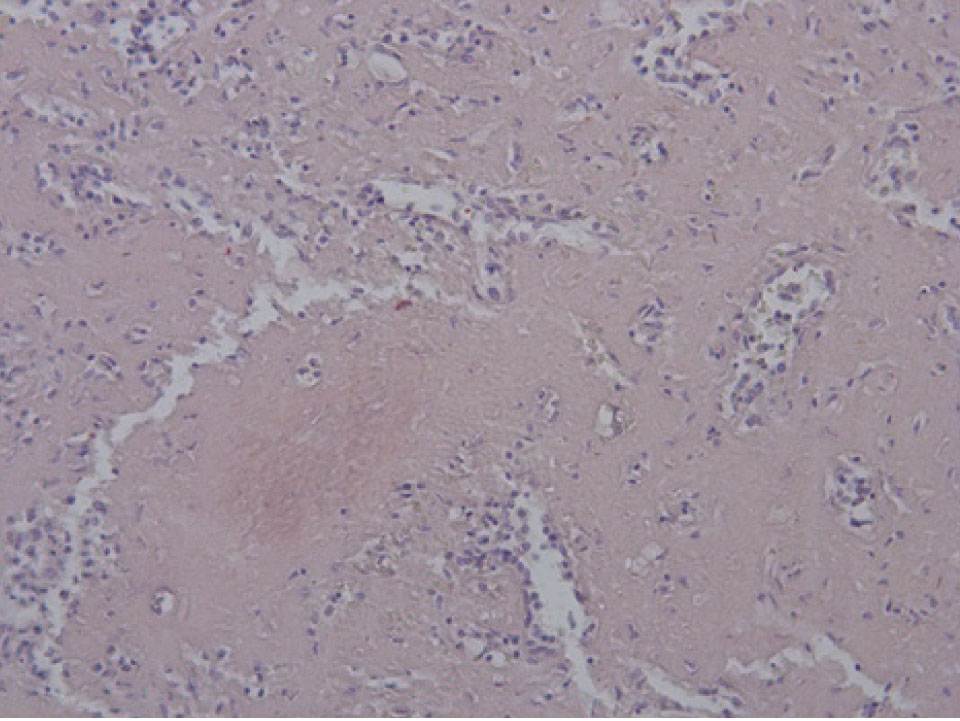

При исследовании ткани легких в стенке сосудов видны плотные гомогенные массы, дающие положительную реакцию на амилоид. При исследовании органов в поляризационном микроскопе обнаружено зеленоватое свечение амилоида. В костном мозге скопление клеток, дающих положительную реакцию с моноклональными антителами к CD38 (рис. 5, 6).

Рис. 5. Пролиферация клеток костного мозга. Окраска гематоксилин-эозин, ×200